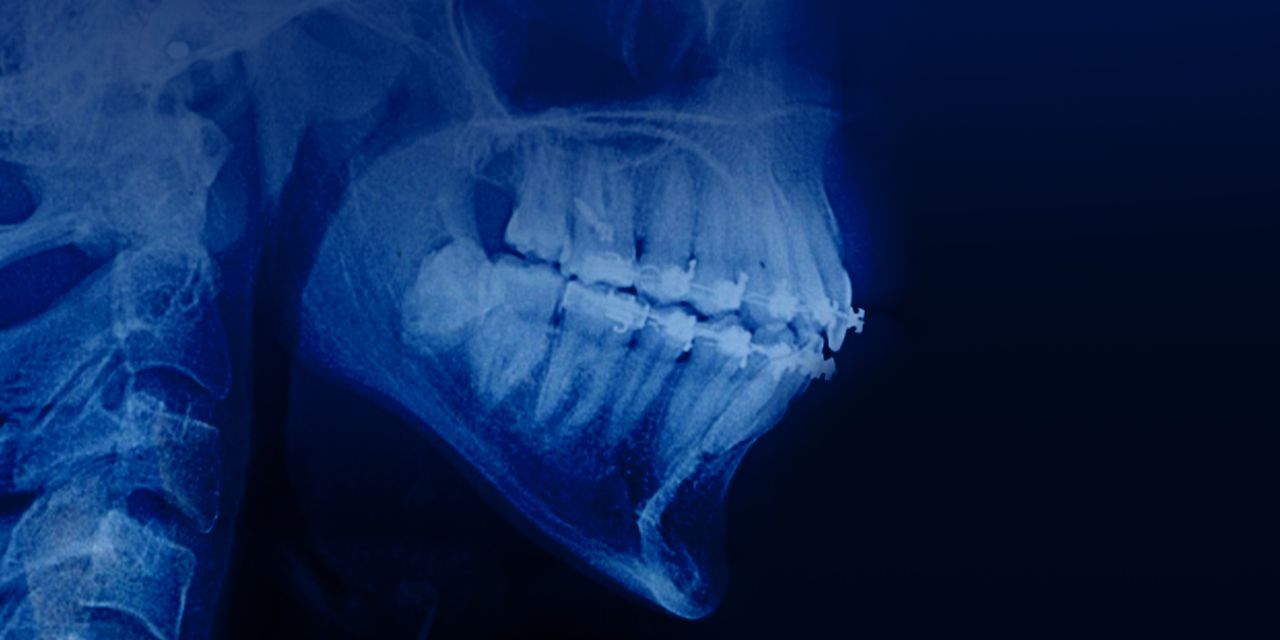

Ортодонтическое лечение у взрослых пациентов с пародонтитом

– Концепция патологической миграции зубов

– Взаимосвязь ортодонтии и пародонтологии

– Лучшее время для ортодонтического перемещения после пародонтальной хирургии

– Биологические принципы ортодонтического перемещения зубов при пародонтозе

– Отдаленные результаты междисциплинарного лечения.